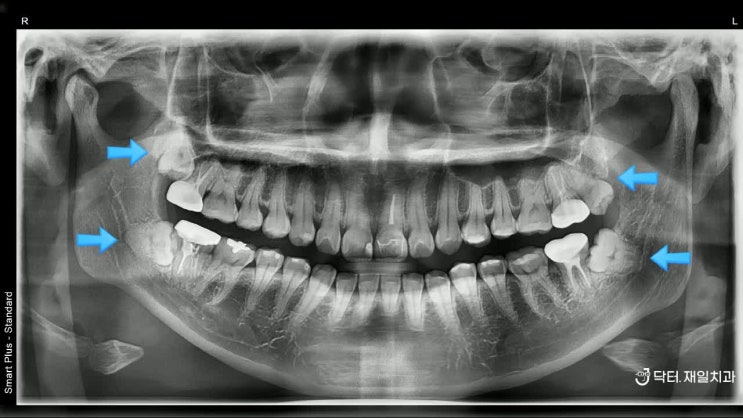

재신경치료 후기를 통한 염증제거 과정과 실패 및 성공률 ! 임플란트 하기 전 마지막 방법 feat. 비용 가격까지

재신경치료 후기를 통한 염증제거 과정과 실패 및 성공률 ! 임플란트 하기 전 마지막 방법 안녕하세요~ 행...